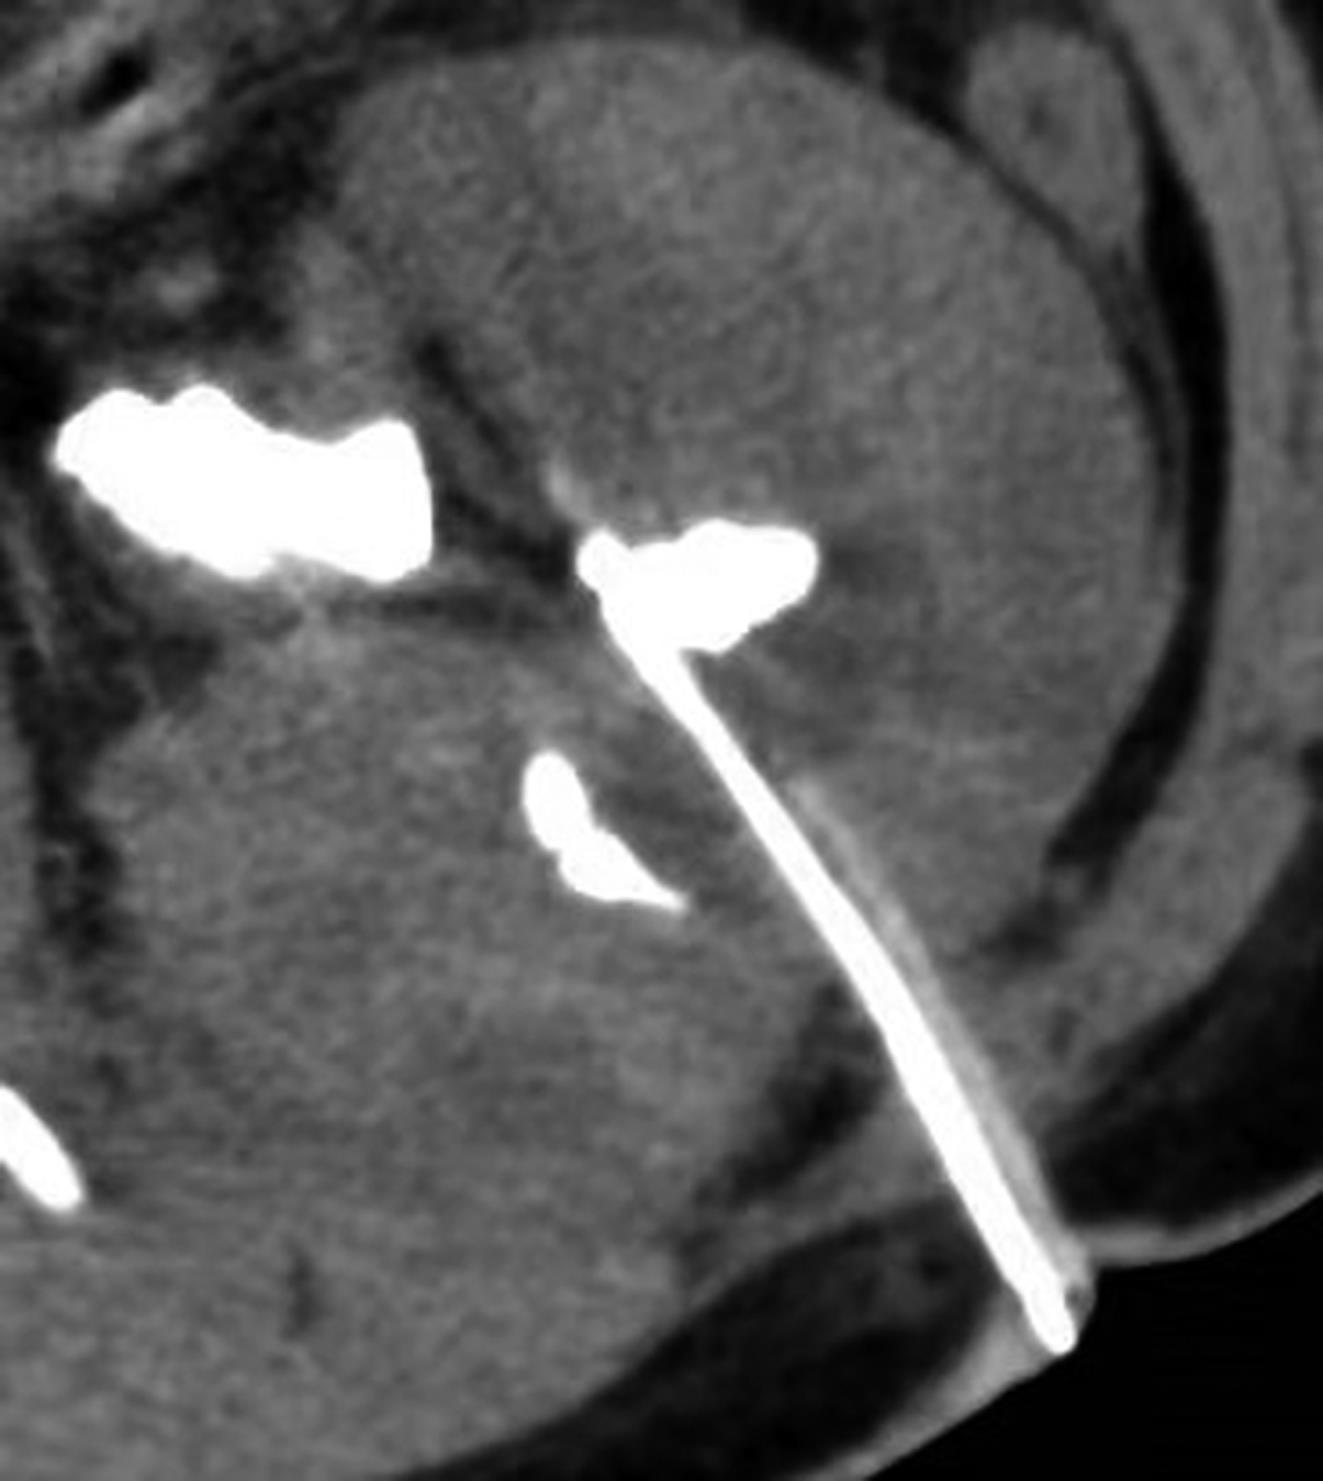

• >临床研究 DOI:10.13406/j.cnki.cyxb.003180

摘要:目的 筛选前列腺癌(prostatic cancer,PCa)发病的影响因素,构建PCa风险预测模型并进行验证。方法 利用国家临床医学科学数据中心《前列腺肿瘤预警数据集》,对数据处理后将数据按7∶3随机分为建模组和验证组;使用最小绝对值收敛和选择算子(least absolute shrink-age and selection operator,LASSO)对建模组进行筛选,得到PCa特征指标;对特征指标进行多因素logistic回归分析,并利用其分析结果对建模组数据构建PCa风险预测模型,同时利用建模组数据进行内部评价及验证组数据内部验证。结果 共纳入880例样本数据,其中建模组616例,验证组264例;通过LASSO回归分析对筛选得到的14个特征指标进行多因素logistic回归分析,结果显示球蛋白(OR=1.112,95%CI=1.044~1.185)、无机磷(OR=65.167,95%CI=20.437~207.796)、总前列腺特异性抗原(total prostate specific antigen,tPSA)(OR=1.026,95%CI=1.014~1.037)与血清尿酸(OR=0.997,95%CI=0.994~0.999)的差异具有统计学意义(P<0.05),是PCa发病的独立影响因素;利用其构建的PCa风险预测模型内部评价和内部验证的校准曲线准确度较高;模型内部评价的曲线下面积(area under curve,AUC)为0.766(95%CI=0.728~0.804),患者的决策曲线分析(decision curve analysis,DCA)净获益率为9%~72%;而模型内部验证的AUC为0.704(95%CI=0.639~0.768),患者的DCA净获益率为18%~59%及63%~64%。结论 球蛋白、无机磷、tPSA与血清尿酸是PCa的独立影响因素,通过其构建的风险预测模型具有良好预测作用。